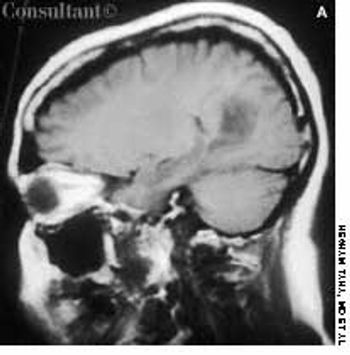

Headache and vomiting suddenly developed in a 41-year-old woman who was 16 weeks pregnant. The next day, she suffered an episode of tonic-clonic seizures associated with a 15-minute loss of consciousness.